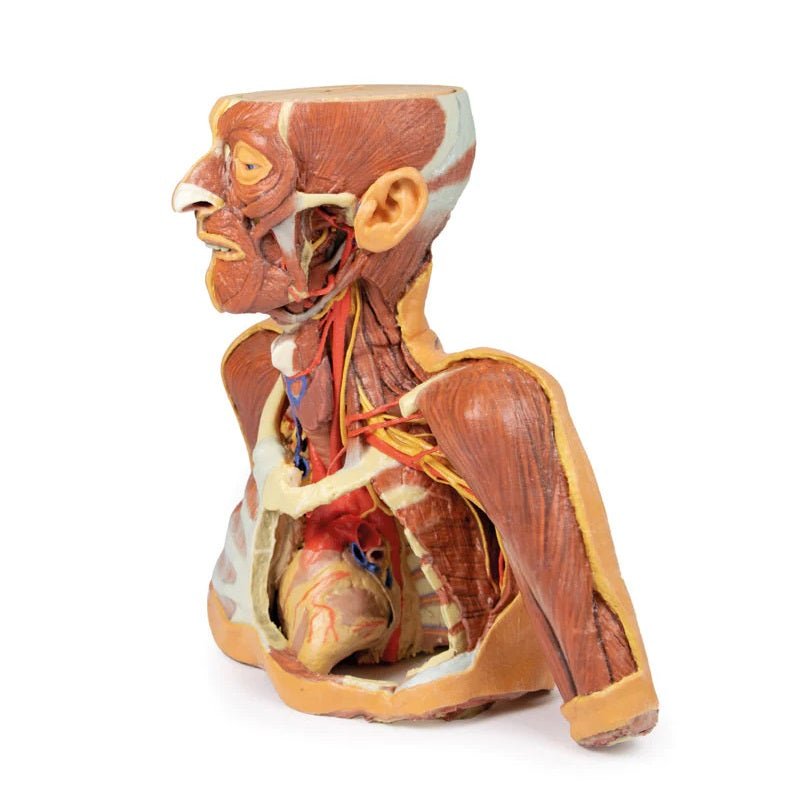

The head and neck of the specimen provides views of both superficial and deep structures in the region. The calotte has been removed ~2cm superior to the orbits to expose the brain in relation to the endocranial cavity. The transverse section through the cerebrum demonstrates the relation of the grey matter cortex to the white matter medulla, as well as the lateral ventricles with a small amount of choroid plexus visible in the base of both spaces. The skin and superficial fascia on the right side has been retained and false-coloured to display the angiosomes of the face and posterior neck. On the left side, the superficial tissues have been dissected to expose the muscles of facial expression, muscles of mastication, and deeper structures of the infratemporal fossa including the lingual nerve, terminal branches of the external carotid artery into the superficial temporal and maxillary arteries.

The carotid sheath has been opened on both sides of the neck, and the internal jugular veins and sternocleidomastoid muscles largely removed, to expose the pathway of the common carotid arteries, internal and external carotid arteries, and the vagus nerves. On the right side, the great auricular nerve ascends towards the face, while the hypoglossal nerve can be seen adjacent to the exposed stylohyoid ligament and supra- and infrahyoid muscles. A large thyroid gland is present bilaterally inferior to the thyroid cartilage, with a well-preserved superior thyroid artery and inferior thyroid vein on the right side and across the midline.

The head and neck of the specimen provides views of both superficial and deep structures in the region. The calotte has been removed ~2cm superior to the orbits to expose the brain in relation to the endocranial cavity. The transverse section through the cerebrum demonstrates the relation of the grey matter cortex to the white matter medulla, as well as the lateral ventricles with a small amount of choroid plexus visible in the base of both spaces. The skin and superficial fascia on the right side has been retained and false-coloured to display the angiosomes of the face and posterior neck. On the left side, the superficial tissues have been dissected to expose the muscles of facial expression, muscles of mastication, and deeper structures of the infratemporal fossa including the lingual nerve, terminal branches of the external carotid artery into the superficial temporal and maxillary arteries.

The carotid sheath has been opened on both sides of the neck, and the internal jugular veins and sternocleidomastoid muscles largely removed, to expose the pathway of the common carotid arteries, internal and external carotid arteries, and the vagus nerves. On the right side, the great auricular nerve ascends towards the face, while the hypoglossal nerve can be seen adjacent to the exposed stylohyoid ligament and supra- and infrahyoid muscles. A large thyroid gland is present bilaterally inferior to the thyroid cartilage, with a well-preserved superior thyroid artery and inferior thyroid vein on the right side and across the midline.